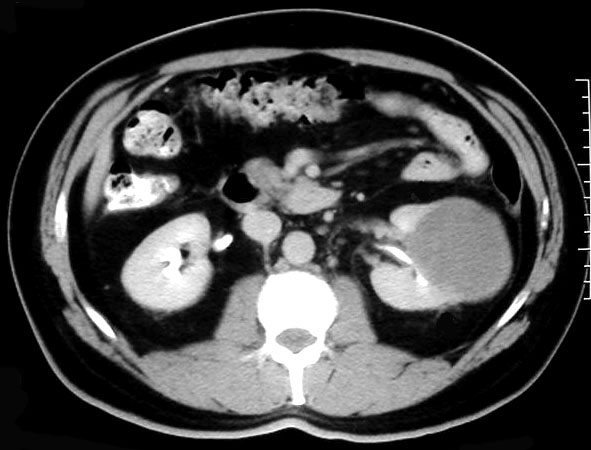

SIGNO VESICAL

Signo visible en la radiografía simple de abdomen que permite diferenciar entre una vejiga muy distendida (globo vesical) y una masa pélvica de otro origen. La distensión de la vejiga se ve como una densidad homogénea redondeada u oval de borde superior definido, que ocupa la pelvis obliterando las zonas laterales de la pelvis y desplazando lateralmente el ciego y el sigma.

Las flechas negras marcan el borde superior vesical bien definido. Obsérvese el borramiento de planos grasos en la pelvis (flecha naranja), el desplazamiento lateral del ciego (flecha blanca) y superior del sigma (flecha roja).